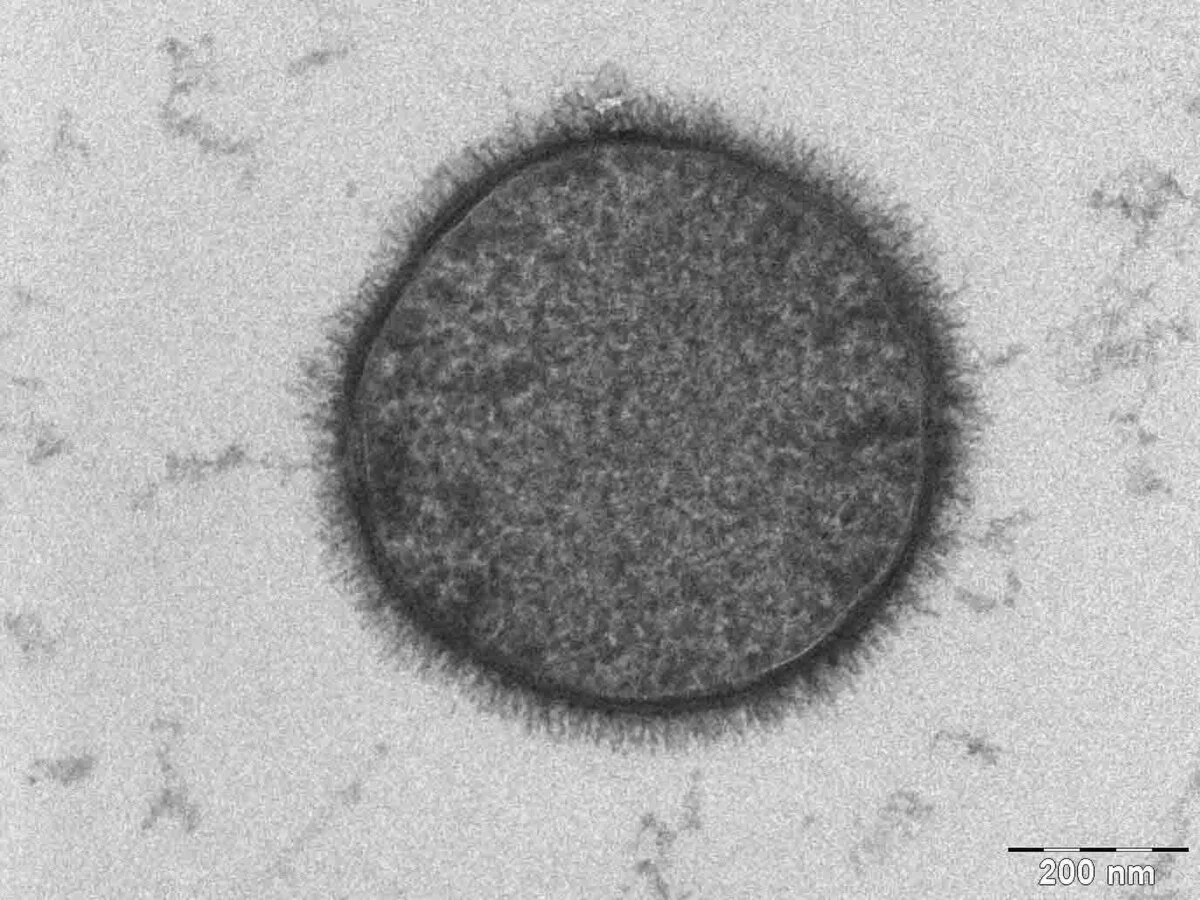

Imaging the Glycocalyx

There are some neat imaging testing methods being developed right now for looking at the endothelial glycocalyx.

One is called the glycocheck and its instruments are noninvasive.

Essentially it's measuring the glycocalyx hair thickness (pretty neat, right?)

They studying with it at some hospitals, research facilities, and universities.